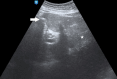

Gastric outlet obstruction in a patient